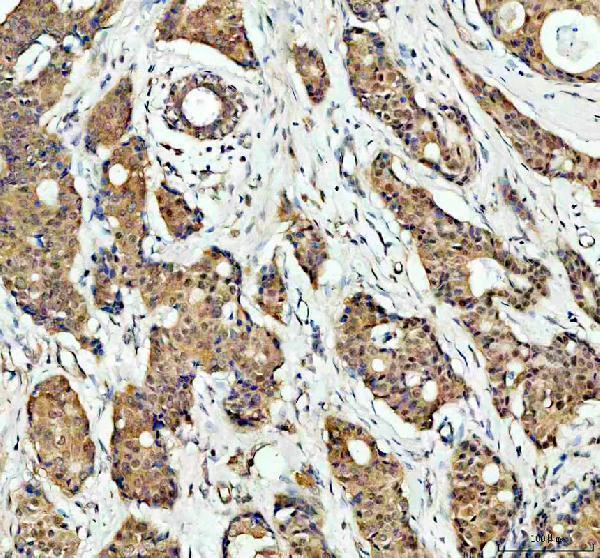

Facts about Mitogen-activated protein kinase 14.

Accordingly, p38 MAPKs phosphorylate a wide assortment of proteins and it has been estimated that they might have approximately 200 to 300 substrates each. A few of the targets are downstream kinases that are activated through phosphorylation and additional phosphorylate additional targets.

Brain, heart, placenta, pancreas and skeletal muscle. Expressed to a lesser extent in lung, liver and kidney.

Cytoplasm. Nucleus.